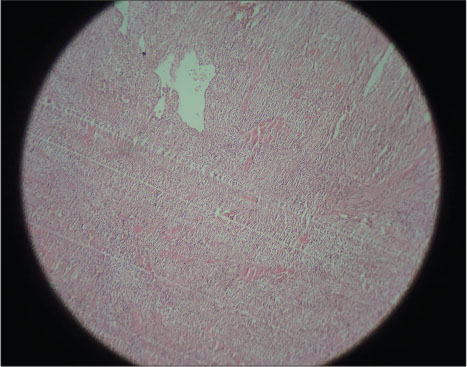

A 4-year-old female patient came with a complaint of growth in the lower back tooth region of lower jaw for 1 week. Parents of the patient noticed the growth a week back which was smaller in size initially which increased suddenly to the present size. Growth was not associated with pain or any other symptoms initially but later developed discomfort while eating associated with mild pain. The patient was given anti-inflammatory medication for the relief of pain and swelling for about 3 days, but there was no reduction in size of the growth. Medical and family histories were noncontributory. On extraoral examination, fullness is seen on the left lower third of face. A solitary left submandibular lymph node enlargement is felt, which is freely movable and tender. Intraorally, an exophytic growth was seen arising from gingiva in relation to 73, 74, and 75 tooth region [Figure 1] measured approximately around size 2 cm × 3 cm, slight pale in color with pinpoint erythematous areas. This appeared to be covered by keratotic surface and seemed to have papillary projections. On palpation, the lesion was pedunculated fibrous inconsistency, nontender, and slight bleeding on provocation, and diascopy test was negative. Considering the patient’s history and clinical examination, a provisional differential diagnosis was arrived which is as follows PG, verrucous hyperplasia, hemangioma, peripheral giant-cell granuloma, peripheral ossifying fibroma, fibroma, and peripheral odontogenic fibroma. The following sets of radiographs were advised to rule out any bony involvement. Intraoral periapical radiograph (IOPA) and occlusal radiographs showed soft-tissue shadow with respect to 73, 74, and 75 [Figure 2] and [3]. Later, complete blood picture was done which did not show any variations from the normal limits. The lesion was subjected for excisional biopsy under local anesthesia [Figure 4] and [5] and subjected to histopathological examination which revealed to be angiomatous granuloma [Figure 6] and [7]. The patient was followed up for 1 year after surgery and there was no evidence of recurrence.

| Figure. 6 Low-power (×10) histopathological section showing numerous hemorrhagic areas and blood vessels in the connective tissue